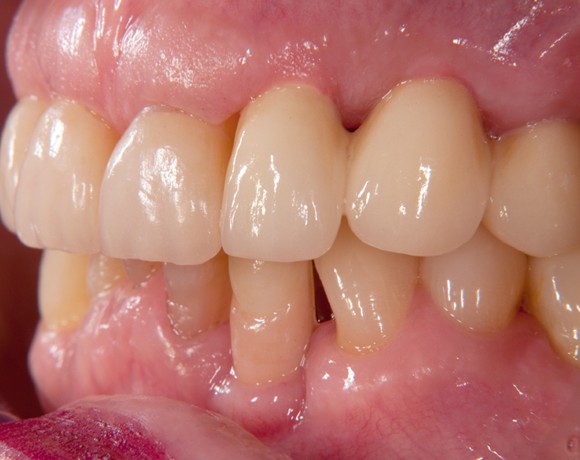

Bei dieser Patientin mussten die Zähne 22,26 und 27 aus parodontalen Gründen entfernt werden. Nach Extraktion der Zähne 22 und 26 wurden sofort in die Extraktionsalveolen die Implantate gesetzt. Zahn 27 war bereits sechs Monate zuvor extrahiert worden und die Knochenwunde gut ausgeheilt. Das geringe Knochenangebot wurde mit einem internen Sinuslift ausgeglichen. Im Bereich des Zahnes 23 wurde noch ein weiteres Implantat gesetzt. Da der Zahn 12 nicht angelegt und die Symetrie auf dieser Seite gestört war, wurden die Zähne 11 und 13 mit Teilkronen versorgt, um die Lücken zu schließen der Zahn 13 zu 12 umgebaut.